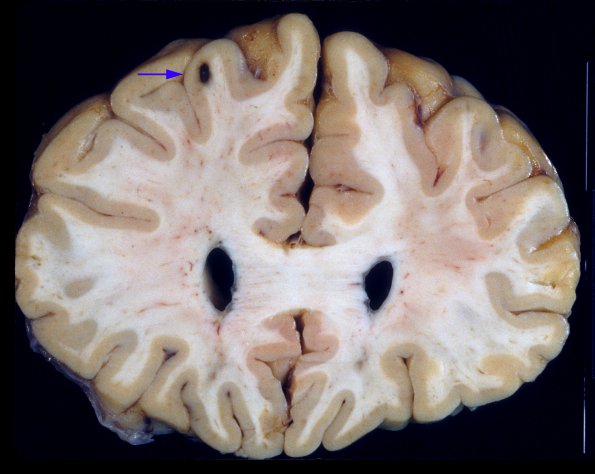

2A2 Histoplasmosis (Case 2) A4 copy

Unexpected hemorrhagic mass (arrow) at the gray-white junction in the frontal lobe.